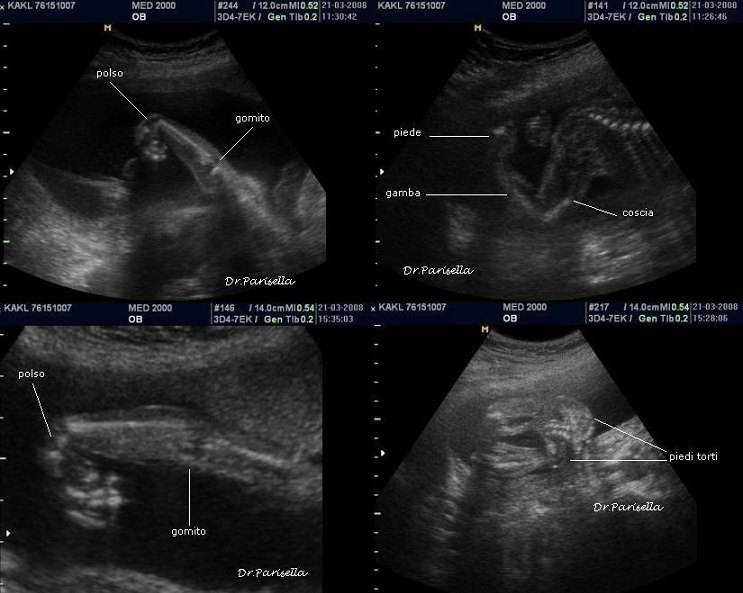

E' caratterizzata da grave ritardo di crescita intrauterino, grave microcefalia, lissencefalia tipo 3  e dismorfismi facciali consistenti in ipertelorismo, micrognazia, grave esoftalmo, anomalie auricolari, naso piatto; una caratteristica è l'edema spiccato che interessa cranio, gomiti, ginocchia, mani e piedi (si ha quasi l'impressione che le dita siano assenti); vi è inoltre assenza dei movimenti attivi fetali (SAF) e possono esservi contratture articolari (artrogriposi) caratterizzate da arti superiori ed inferiori in flessione.

I segni ecografici sono numerosi :

1. IUGR

4. edema spiccato,

5. assenza di movimenti attivi fetali (SAF),